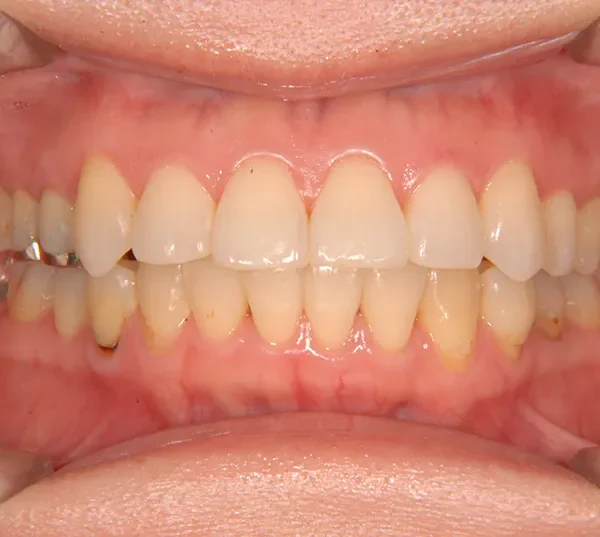

• 治療終了後

治療終了後

上下のがたがたと噛み合わない事を主訴に来院されました。

歯は抜かずに矯正治療しました。

治療回数35回、2年8ヶ月の治療期間で矯正治療を終了しました。

噛み合わせが安定する事で、大きくなっていた咬筋が正常な大きさになり、顎のラインもシャープになり大変よろこばれていました。